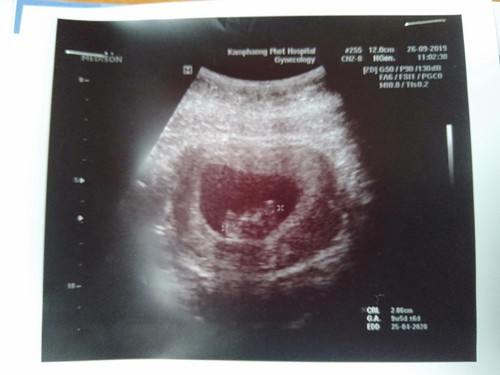

ภาวะเสี่ยงเบาหวานขณะตั้งครรภ์

ตรวจเลือดแล้วเจอน้ำตาลในเลือดสูง ต้องทำไงบ้างคะอีกหนึ่งอาทิตย์หมอนัดเจาะเลือดอีกครั้ง ปกติเปนคนไม่ทานหวาน มันเกิดจากอะไร น้ำตาลในเือดที่เจอ144 แม่ๆทำไงกันบ้างคะ น้องอายุครรภ์ 10+6คะ